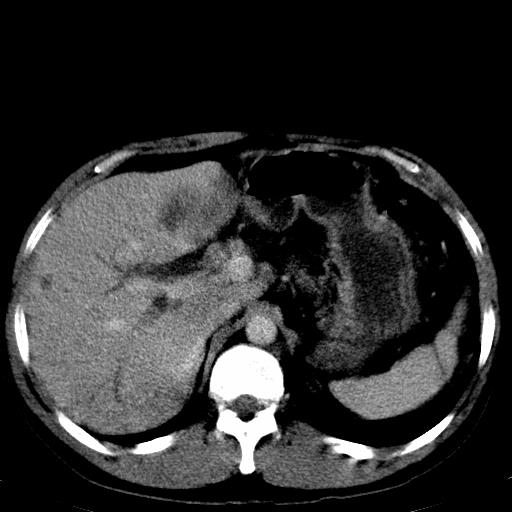

患者上腹部疼痛一月余,伴巩膜黄染;

实事求是的说,强化效果很一般,重点部位应重点观察,但有一点可以明确:肝门部胆管细胞癌。

考虑肝左叶胆管细胞癌侵犯肝门区并肝内胆管及肝总管扩张。

肝左叶肿块清度增强,所在的叶胆管扩张。考虑胆管细胞癌。

考虑肝左叶胆管细胞癌侵犯肝门区并肝内胆管及肝总管扩张、肝门淋巴结肿大。